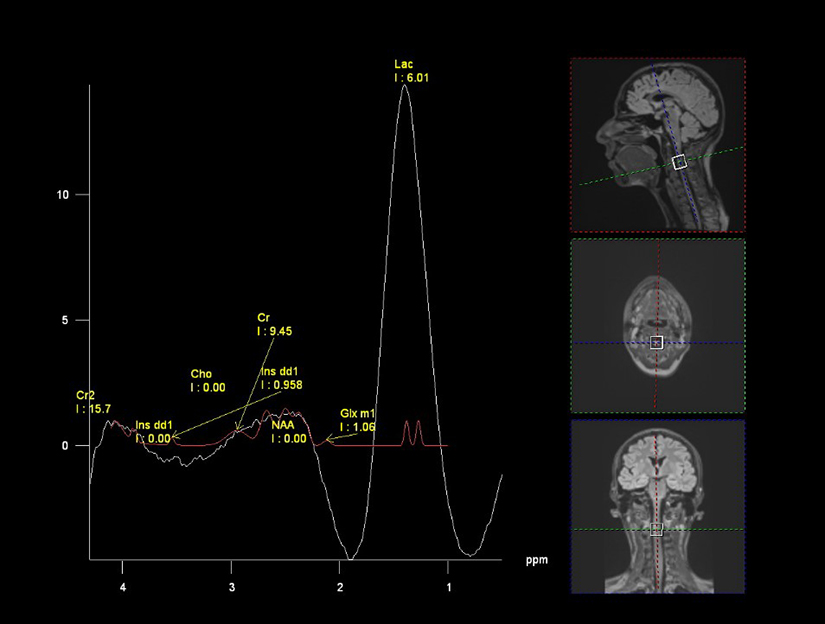

Spectroscopia de rezonanta magnetica (MR Spectroscopy) este un examen imagistic noninvaziv care masoara modificarile biochimice din tesuturi, in special la nivel cerebral. Este efectuata folosind acelasi aparat de rezonanta magnetica nucleara ca in cazul examenul RMN conventional, dar se utilizeaza o serie de teste suplimentare (secvente) care ofera informatii despre metabolismul si structura biochimica a tesuturilor, astfel incat medicul imagist poate determina tipul de tesut prezent.

Spectroscopia este o investigatie imagistica complexa din punct de vedere tehnic – poate predispune la artefacte, iar procesarea si interpretarea necesita expertiza.

Spectroscopia este folosita in special pentru evaluarea tumorilor cerebrale. In timp ce RMN cerebral conventional identifica localizarea anatomica a tumorii, permitand diagnosticul diferential al unor leziuni cerebrale. Spectroscopia cerebrala compara compozitia chimica a tesutului normal cu cea a celulelor anormale. Testul este folosit in special pentru a determina tipul tumorii si gradul de agresivitate si pentru a distinge intre recurenta tumorii si necroza de iradiere.

Glioame: spectroscopia creste abilitatea de a prezice gradul tumorii. Pe masura ce gradul creste, nivelele de N-acetil aspartat (NAA) si creatinina scad, in timp ce nivelele de colina, lipide si lactat cresc.

Necroza postiradiere: spectroscopia ajuta la diferentierea intre modificarile cauzate de recurenta tumorii, cand creste colina, si cele datorate radioterapiei, in care NAA, colina si creatinina sunt toate scazute.

Ischemia cerebrala si infarctul cerebral: spectroscopia urmareste evolutia lactatului in teritoriul cerebral afectat - trecerea la metabolismul anaerobic va determina cresterea lactatului, iar odata aparuta necroza celulara (infarctul cerebral), se elibereaza si cresc lipidele.

Infectie: din cauza ca celulele nervoase normale sunt distruse, NAA va fi absent. In cavitatea unui abces cerebral, nivelele de lactat, alanina si acetat vor fi crescute.